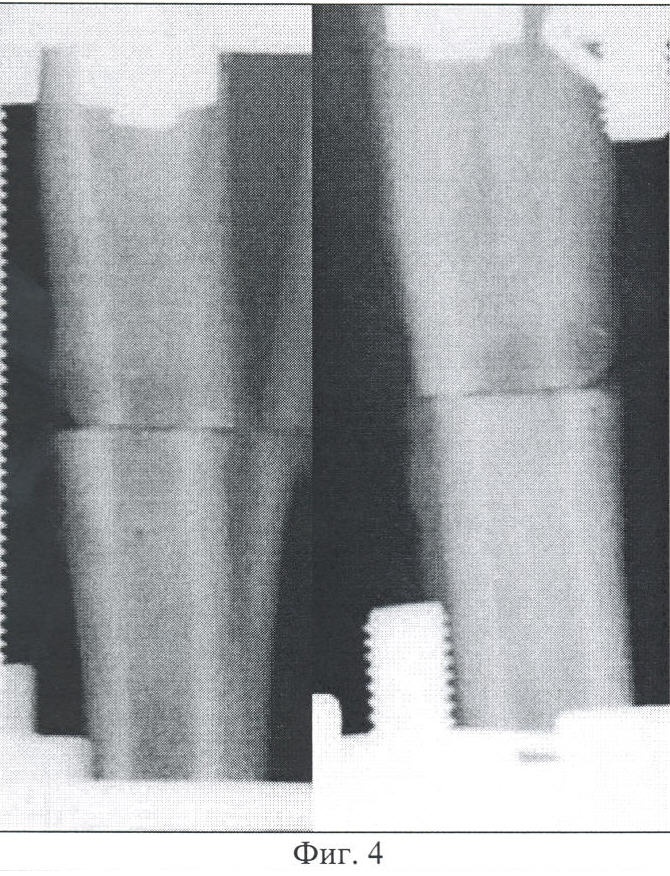

Фиг.4 – копия рентгенограммы костей голени согласно изобретению, 7 суток фиксации после компрессии.

Через 7 суток после компрессии рентгенологически контуры концов отломков нечетко выражены. Межотломковую щель перекрывают гомогенные тени низкой интенсивности. В проекции костномозговых полостей отломков выявляется эндостальная реакция. Периостальная – характеризуется наличием на отломках рыхлых теней толщиной до 2,0 мм и протяженностью 0,5-1,7 см от линии остеотомии, более выраженных на дистальном отломке (Фиг.4).